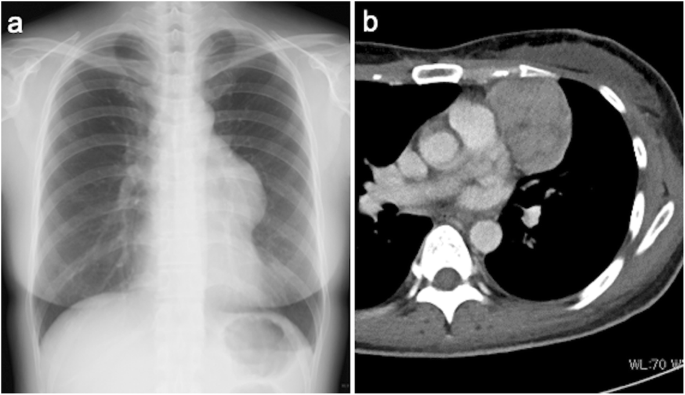

The patient was a 45-year-old woman who was referred to a nearby clinic for fever of 38 °C, cough, and nasal discharge. Although she was treated with antibiotics, her signs were not improved. Chest X-ray and computed tomography showed a 61 × 45-mm anterior mediastinal tumor (Fig. 1). Positron emission tomography scan showed 1.8-fold greater uptake than the maximal standardized uptake value in the tumor. A blood test revealed a serum immunoglobulin G level of 239 mg/dL (normal range 870–1700 mg/dL), serum immunoglobulin A level of 24 mg/dL (normal range 110–410 mg/dL), and a serum immunoglobulin M level of 26 mg/dL (normal range 46–260 mg/dL). She was referred to our hospital for further examination and treatment for the anterior mediastinal tumor and hypogammaglobulinemia. The histopathological diagnosis of a CT-guided biopsy specimen was type AB thymoma based on the World Health Organization classification, leading to the diagnosis of Good syndrome.